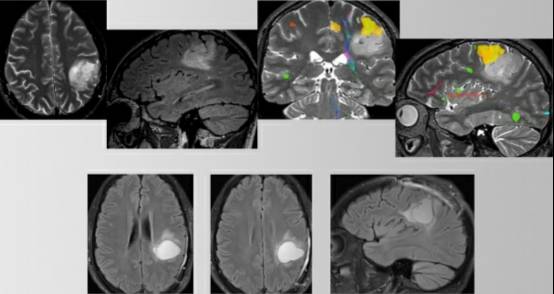

图1. 中央沟的影像学标志。源自于额上沟(绿色箭头)水平部末端向后的第二条垂直脑沟的是中央沟(红色箭头)(左图)。更多可靠的定位方法如下:先在正中矢状位MRI找到扣带沟(绿色箭头),然后向上(边缘沟)直至大脑边缘。边缘沟位于Rolandic区(中央小叶:红色箭头包绕区)后方,(右图)。

图2. 紧靠运动区前方的肿瘤需要使用运动功能区定位,确保肿瘤最大程度的安全切除。额上沟(蓝色箭头),中央沟(红色箭头)(左图)。fMRI提示位于中央小叶前部和内侧的肿瘤(中图)。术后MRI显示占位病变全切(右图)。该患者术后出现暂时性足部无力,4周后完全缓解。发生任何永久性的神经功能障碍都会削弱或消除由手术切除肿瘤带来的任何生存优势。由于肿瘤直接浸润运动功能区,有必要使用唤醒型功能区定位,术中定期检查,确保和判断肿瘤安全切除的范围。

图6. 术前MRI和fMRI提示病变位于运动功能区后部和下部(黄色)(第一行)。脑皮层和皮层下唤醒定位切除占位(第二行)。术腔前部稍高T2高信号,可能是残余肿瘤;脑皮层下定位提示该区域有运动纤维束存在,放弃进一步切除该区域病灶。